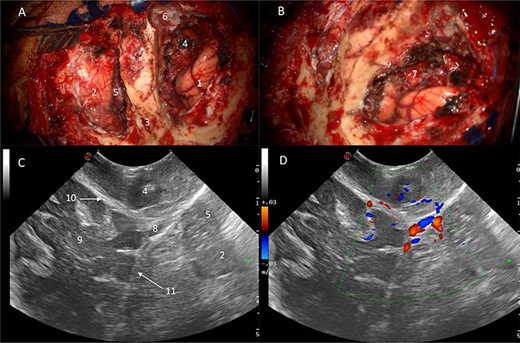

Power and colour Doppler were used throughout to obtain real-time information about the location and function of dural venous sinuses. Blood flow was preserved in the sinuses and, as we debulked the tumour, we were able to demonstrate bi-directional flow within the sinuses (Fig. 3). This suggested resolution of venous obstruction and indicated the dural venous sinuses had regained their functionality. Medially tumour was found invading the torcula and right transverse sinus, and a decision was made to leave the residual tumour and to preserve the sinuses (Fig. 4). We achieved a Simpson Grade 4 resection without any intraoperative complications.

Intraoperative images at the end of resection; Duplex US images (2D image with overlay of colour Doppler) of the initial appearances of the straight sinus (A) and appearance at the end of resection (B); a bidirectional flow in the straight sinus is apparent after tumour resection, this was not present prior to tumour debulking; the Triplex Doppler confirms the bidirectional flow in the straight sinus (C and D).